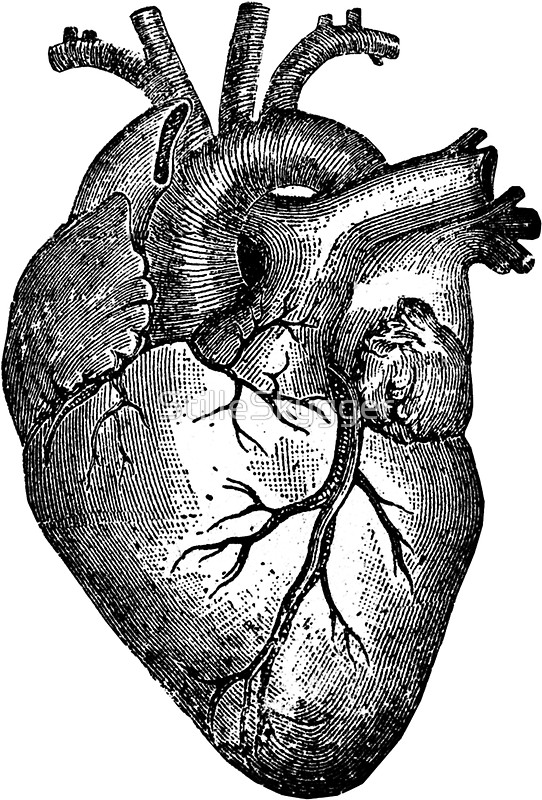

1500x904 Anatomical Drawing Of A Heart Anatomy Drawings Heart Medical

2454x3657 Anatomical Drawing Of A Heart Drawings Of Human Hearts To Draw

1300x866 Human Heart, Anatomical Heart Hand Drawn Vector Illustration

1024x1024 Anatomical Heart Medical Illustration Heart Medical Illustrations

1405x1920 Anatomical Heart Medical Illustration Human Heart Free Stock Photo

713x1023 Heart. The Internal Human Organ, Anatomical Structure. Stock

951x1390 Human Heart Black And White Stock Photos Amp Images

533x800 Human Heart Outline Sketch. Isolated Anatomical Detailed Organ

1300x1300 Vector Illustration Of Human Heart. Anatomy Drawing Made

1300x1300 Vector Realistic Anatomical Heart Royalty Free Cliparts, Vectors